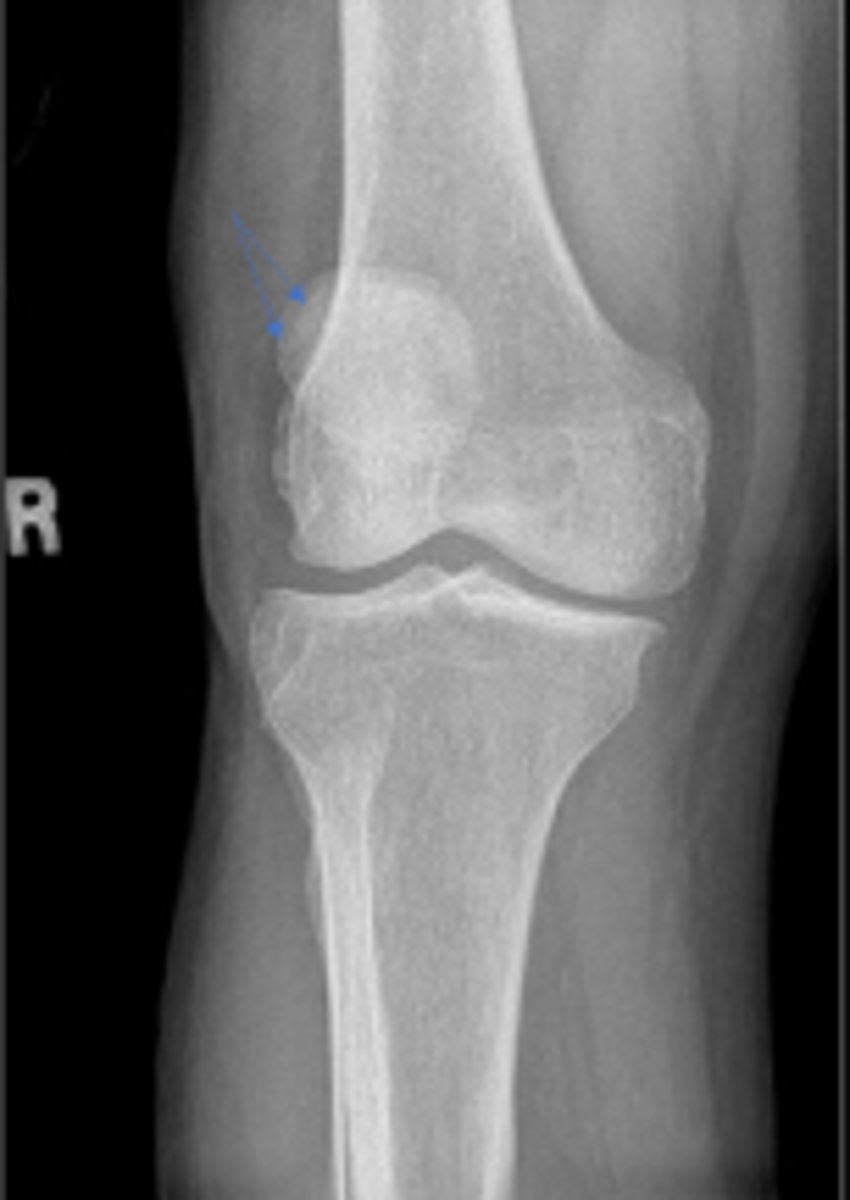

Right AP knee

What is the name of the radiographic view?

Right adductor tubercle

What tubercle is pointed to by the arrow?

Lateral epicondyle of the right femur

What is the arrow pointing to?

Medial epicondyle of the right femur